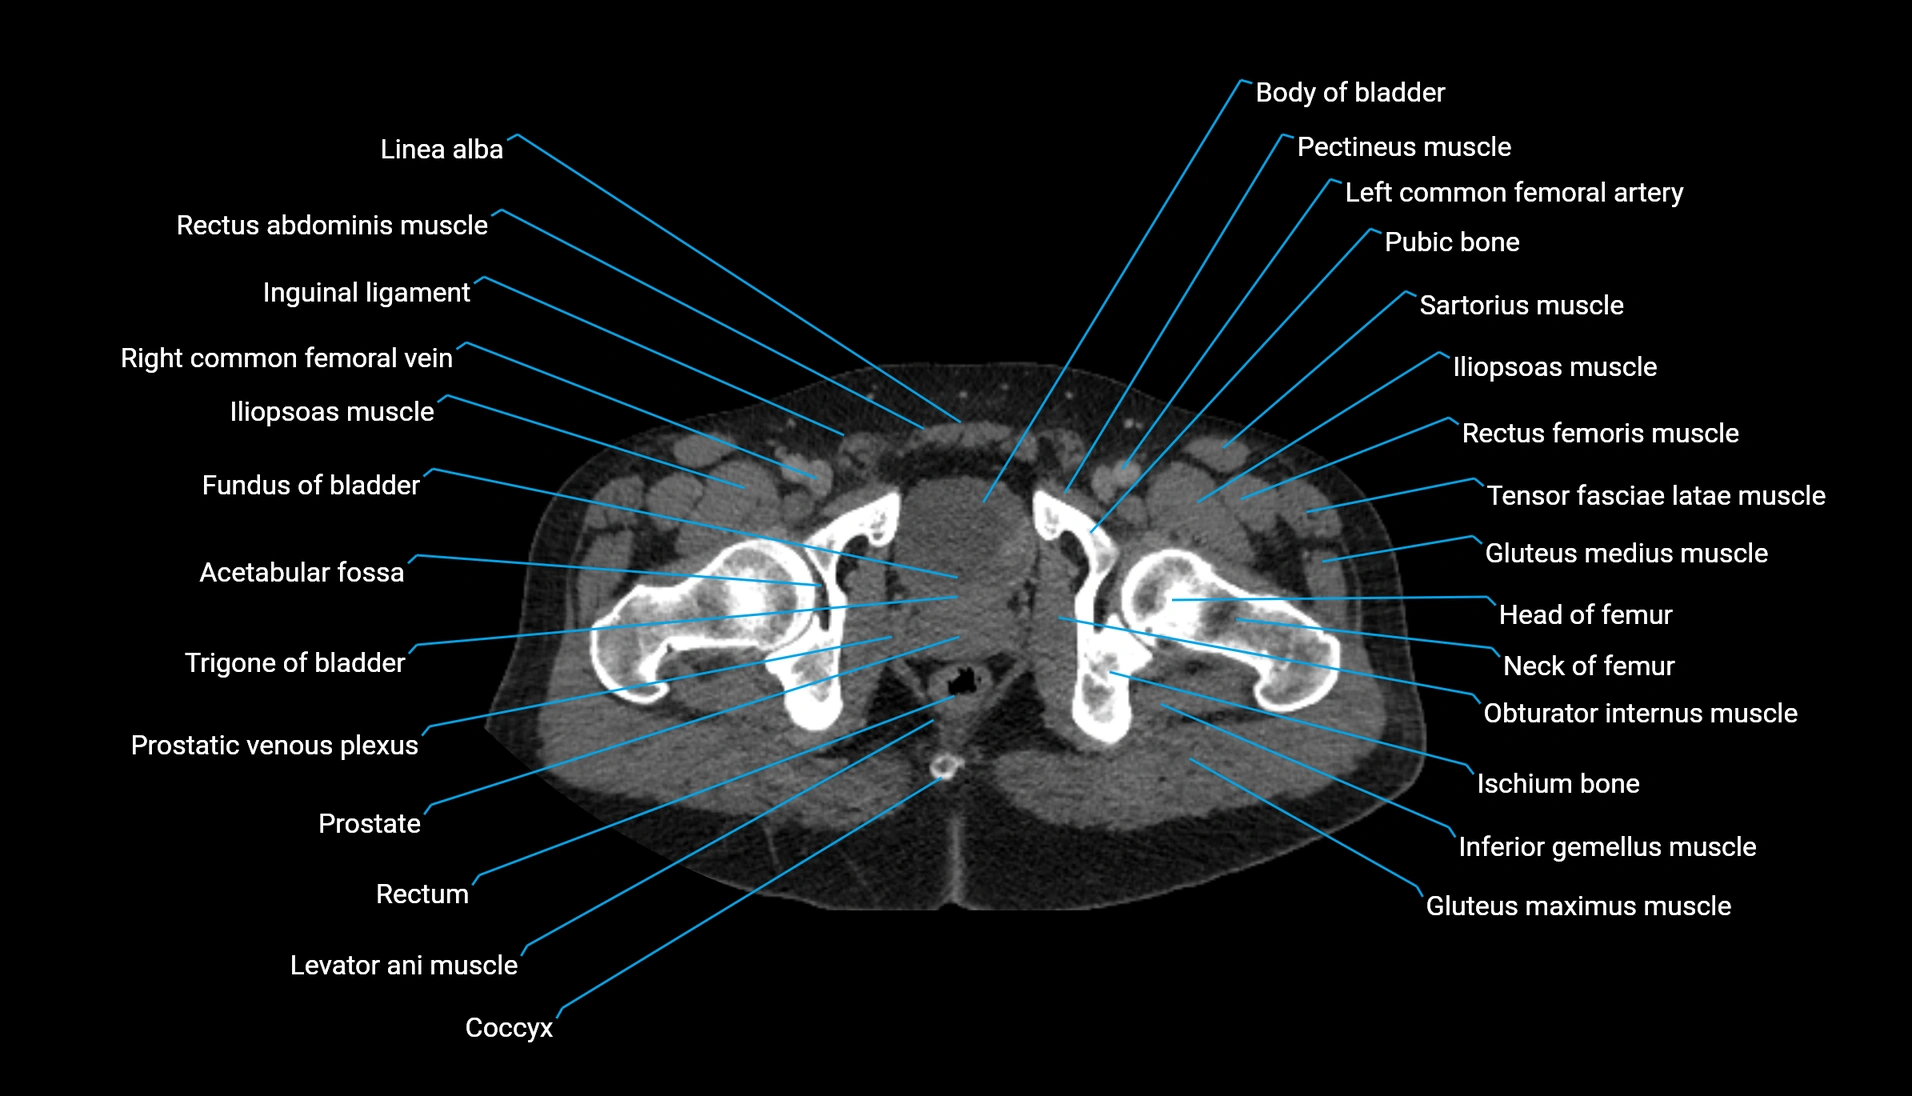

CT Appearance

Non-contrast CT:

-

Demonstrates cortical bone of acetabular rim in excellent detail

Detects fractures, dysplasia, retroversion, or bony overcoverage (pincer impingement)

3D reconstructions used in preoperative hip surgery planning

CT image